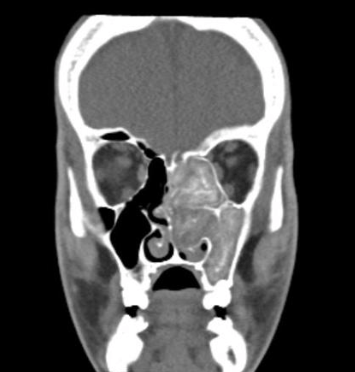

To study the effectiveness of sole Itraconazole therapy in patients with AFRS by comparison of clinical, radiological, and biochemical parameters before and after treatment.

Thirty-four patients diagnosed with localized sino-nasal AFRS were recruited and started on the tablet Itraconazole 200 mg orally twice daily for 3 months with q2weekly monitoring of liver function tests. The baseline clinical, radiological, and biochemical parameters were then compared with those after completion of 3 months of Itraconazole therapy.

There was significant difference between all the parameters—clinical: SNOT-22 score (p < 0.001) and Meltzer endoscopy score (p < 0.001), radiological: Lund-Mackay score (p = 0.004) and 20-point CT score (p = 0.002), and biochemical: serum total IgE (p < 0.001), Aspergillus-specific IgE (p < 0.001), and absolute eosinophil count (p < 0.001). The clearance of the disease was more in anterior sinuses than the posterior ones.